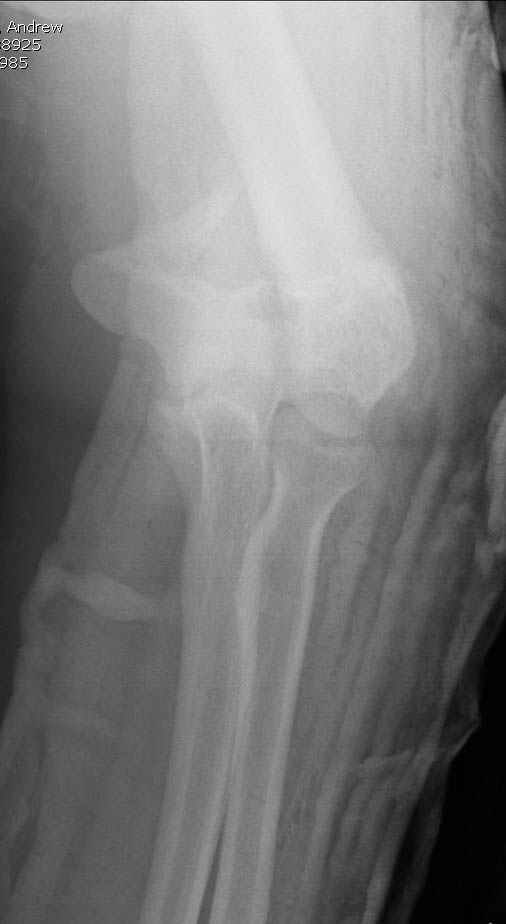

Уважаемые коллеги! Мужчина, 28 лет. 1 сутки назад получил бытовую травму - закрытый чрезмыщелковый перелом правой плечевой кости со смещением. По месту жительства в ЦРБ - репозиция, иммобилизация. Направлен к нам.

Солидарен с мнением обоих Александров (Челнокова и Рыкова): точную репозицию такого перелома вряд ли удастся выполнить закрыто. Даже во время открытого вмешательства это сделать непросто. Неслучайно предложен костно-пластический доступ с временным отсечением локтевого отростка. И по методу фиксации согласен с Александром Челноковым: 2 пластины. В качестве примера привожу рентгенограммы одного из наших пациентов с аналогичным повреждением.

Примерный случай, только перелом был открытый, в задне-медиальной стороне рана около 2 см по характеру "изнутри кнаружи", неврологический статус со слабостью сгибания мизинца, также слабая абдукция и аддукция указательного пальца и сгибания в кисти.

Больному сделали обработку и наложили временный аппарат внешной фиксации плечо-предплечье.

На шестой день сделали открытую репозицию чрезлоктевым доступом двумя locking plate, локтевой нерв был ушибленным, после операции положительная динамика в Flexor Carpi Ulnaris. Фиксацию локтевого отростка произвели tension band technique с дополнительным шурупом.

Этапы операции на снимках....